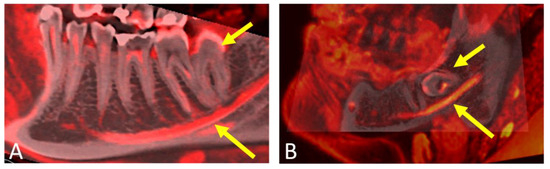

- Al-Haj Husain, A.; Solomons, M.; Stadlinger, B.; Pejicic, R.; Winklhofer, S.; Piccirelli, M.; Valdec, S. Visualization of the Inferior Alveolar Nerve and Lingual Nerve Using MRI in Oral and Maxillofacial Surgery: A Systematic Review. Diagnostics 2021, 11, 1657. [Google Scholar] [CrossRef] [PubMed]

- Al-Haj Husain, A.; Stadlinger, B.; Winklhofer, S.; Müller, M.; Piccirelli, M.; Valdec, S. Mandibular Third Molar Surgery: Intraosseous Localization of the Inferior Alveolar Nerve Using 3D Double-Echo Steady-State MRI (3D-DESS). Diagnostics 2021, 11, 1245. [Google Scholar] [CrossRef] [PubMed]

- Fujii, H.; Fujita, A.; Yang, A.; Kanazawa, H.; Buch, K.; Sakai, O.; Sugimoto, H. Visualization of the Peripheral Branches of the Mandibular Division of the Trigeminal Nerve on 3D Double-Echo Steady-State with Water Excitation Sequence. AJNR Am. J. Neuroradiol. 2015, 36, 1333–1337. [Google Scholar] [CrossRef]

- Al-Haj Husain, A.; Valdec, S.; Stadlinger, B.; Rucker, M.; Piccirelli, M.; Winklhofer, S. Preoperative visualization of the lingual nerve by 3D double-echo steady-state MRI in surgical third molar extraction treatment. Clin. Oral Investig. 2022, 26, 2043–2053. [Google Scholar] [CrossRef]